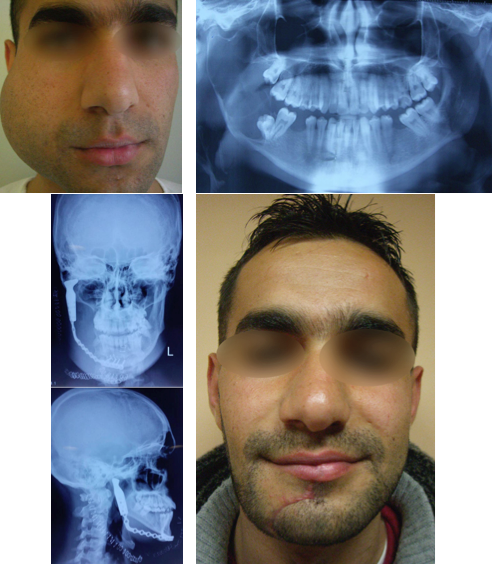

Η αναδόμηση του προσώπου, συντηρητική ή χειρουργική, είναι οποιαδήποτε επέμβαση που αποκαθιστά τα χαρακτηριστικά του προσώπου. Οι επεμβάσεις αυτές που είναι κυρίως χειρουργικές, μπορούν να βελτιώσουν αισθητικές παρεκκλίσεις ή να επιδιορθώσουν παραμορφώσεις που οφείλονται σε τραυματισμό, μη φυσιολογική ανάπτυξη – σύνδρομα, μολύνσεις, νεοπλασίες, εγκαύματα, ή οποιαδήποτε άλλη παραμόρφωση του προσώπου.

Οι τεχνικές αναδόμησης μπορεί να είναι ελάχιστα επεμβατικές με τοποθέτηση υλικών – μοσχευμάτων διαφόρων ειδών, LASER, ή χειρουργικές. Ο κύριος λόγος αναδόμησης του προσώπου αφορά αισθητικές απαιτήσεις όπου αποτελούν και τον μεγαλύτερο αριθμό. Δεν είναι όμως λίγες και οι παρεμβάσεις που αφορούν τους τραυματισμούς (πχ ατυχήματα τροχαία, εργατικά, αθλητικά, βιαιοπραγίες) και τα σύνδρομα.